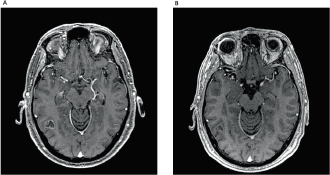

Here, we report a 53-year-old male, never-smoked patient, who had undergone left lower lobectomy and mediastinal sampling for lung adenocarcinoma, pathologic stage IIIC (T3N3M0), harbouring an EGFR exon 19 deletion (p.Leu747_Ala750delinsPro; NM_00528), detected by pyrosequencing (PyroMark Q24, Qiagen, Tokyo, Japan). Post-surgical 18-fluorodeoxyglucose positron emission tomography/computerized tomography revealed positive upper and lower contralateral (right) paratracheal nodes. Definitive concurrent chemoradiation (54 Gy delivered concurrently with cisplatin 50 mg/m2 on days 1, 8, 29 and 36, plus etoposide 50 mg/m2 daily on days 1–5 and 29–33) was administered up to February 2018, followed by durvalumab 10 mg/kg, starting in April 2018. After eleven 14-day cycles, he complained of a new-onset headache. Brain MRI revealed widespread supra and infratentorial brain parenchymal metastasis, and he underwent surgical resection of two bilateral frontal metastases (left 4.1 cm and right 2.8 cm), which confirmed EGFR-mutant lung adenocarcinoma, harbouring the same EGFR exon 19 deletion (p.Leu747_Ala750delinsPro; NM_00528). Twenty-two days after durvalumab interruption, osimertinib 80 mg once daily was initiated. On the 53rd day of osimertinib treatment, the patient was admitted due to intense dyspnoea on exertion and cough. Chest CT scan revealed patchy ground-glass opacities (Figure 1). As interstitial lung disease induced by osimertinib was considered, EGFR-TKI was suspended and prednisone 1 mg/kg/day was started, along with piperacillin-tazobactam. Three weeks later, a new CT scan showed significant improvement and all symptoms subsided. Patient was rechallenged with osimertinib 40 mg, 42 days after its suspension, and prednisone was rapidly tapered down. As of today, 2 months after this rechallenge, new brain MRI showed tumour response, including shrinkage in the right occipitotemporal lesion (0.8 cm × 0.5 cm; previously 1.8 cm × 1.4 cm) (Figure 2) and the left cerebellar lesion (0.5 cm; previously 1.1 cm × 0.8 cm). No signs of pneumonitis recurrence were noticed.

Figure 2. (A): Brain MRI demonstrating right occipitotemporal lesion measuring 1.8 cm × 1.4 cm. (B): Two months after rechallenge of osimertinib and reduction of the lesion, measuring 0.8 cm × 0.5 cm.